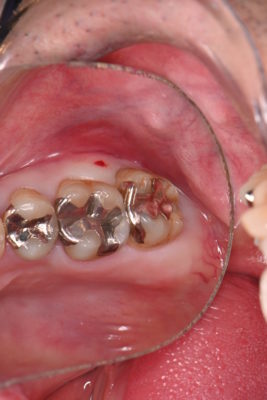

今回は右上の1番奥の歯をMTAセメント治療された方をご紹介します!

こちらの患者様は30代男性の方で奥歯が欠けてしまったと来院されました。

銀歯の下が虫歯でもろくなって欠けてしまったようです・・・

痛みなどの症状がなかったので、神経を極力残せる治療をご提案させていただきました。